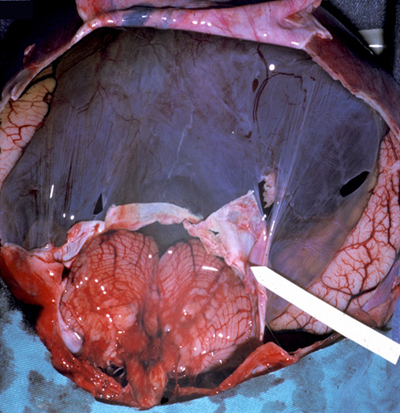

- Hydranencephaly

- "hydro-anencephaly"

- severe, diffuse necrosis of the cerebral mantle leading to ex vacuo hydrocephaly

- cerebral mantle replaced by floating membrane of thickened leptomeninges and the remnant of the underlying necrotic cerebral mantle

- only remaining components: medial temporal lobes, caudal thalamus (posterior circulation), cerebellum (may be cystic also)

- cystic or atrophic olfactory and optic nerves, pituitary tract, basal ganglia

- secondary atrophy of brainstem and spinal cord

- due to internal carotid distribution perfusion failure before 15-16 wks GA

- etiologies include maternal trauma, twin-twin transfusion syndrome, massive hemorrhage, familial vascular malformations (proliferative glomeruloid vasculopathy)